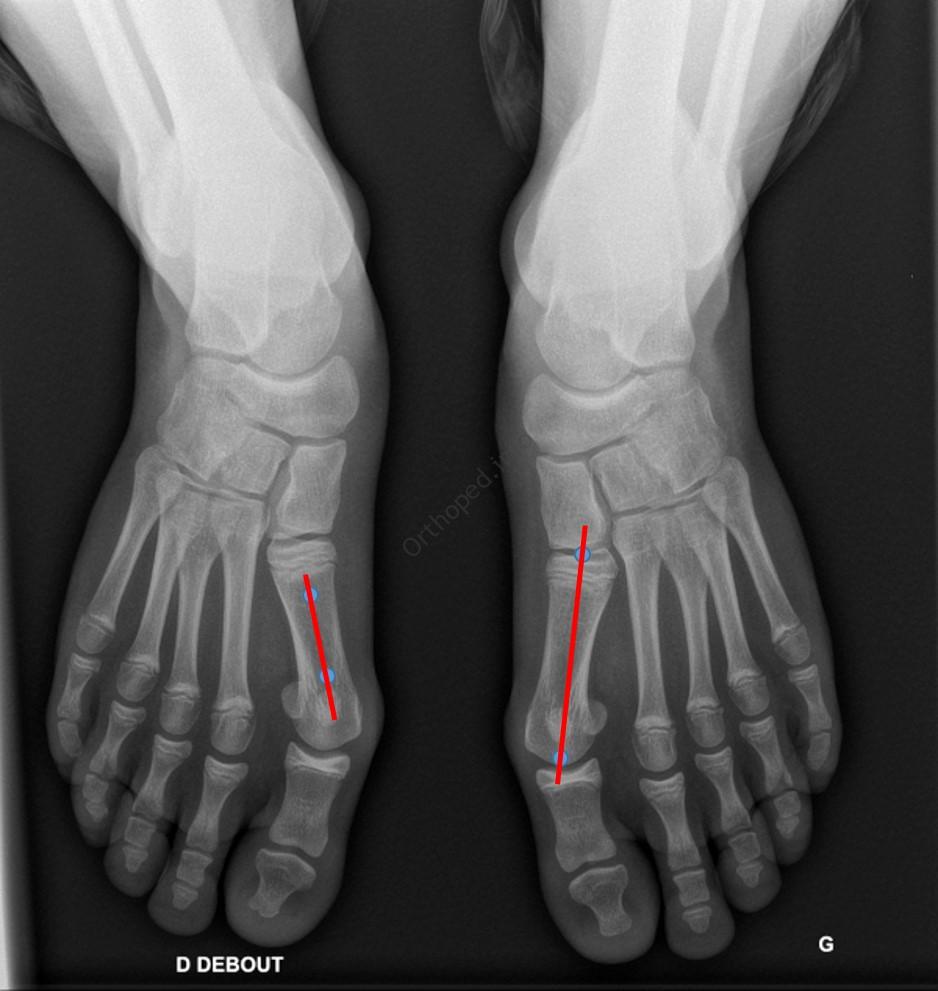

L’évaluation radiographique de l’hallux valgus se fait sur une radiographie de Face du pied en charge.

Il faut d’abord tracer l’axe des métatarsiens :

- soit l’axe diaphysaire : ligne qui relie 2 points situés au milieu de la diaphyse (pied D, à G sur l’image)

- soit l’axe épiphysaire : ligne qui relie le centre des surfaces articulaires (pied G, à D sur l’image)